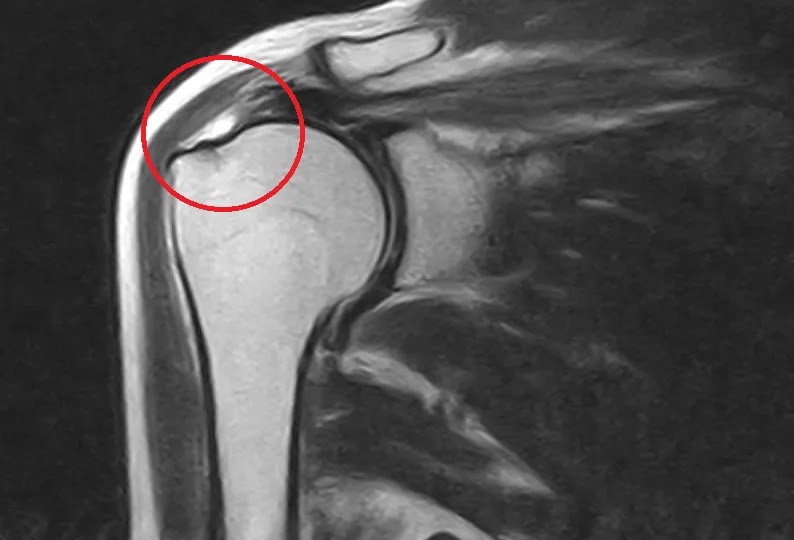

腱板損傷

Rotator Cuff Injury